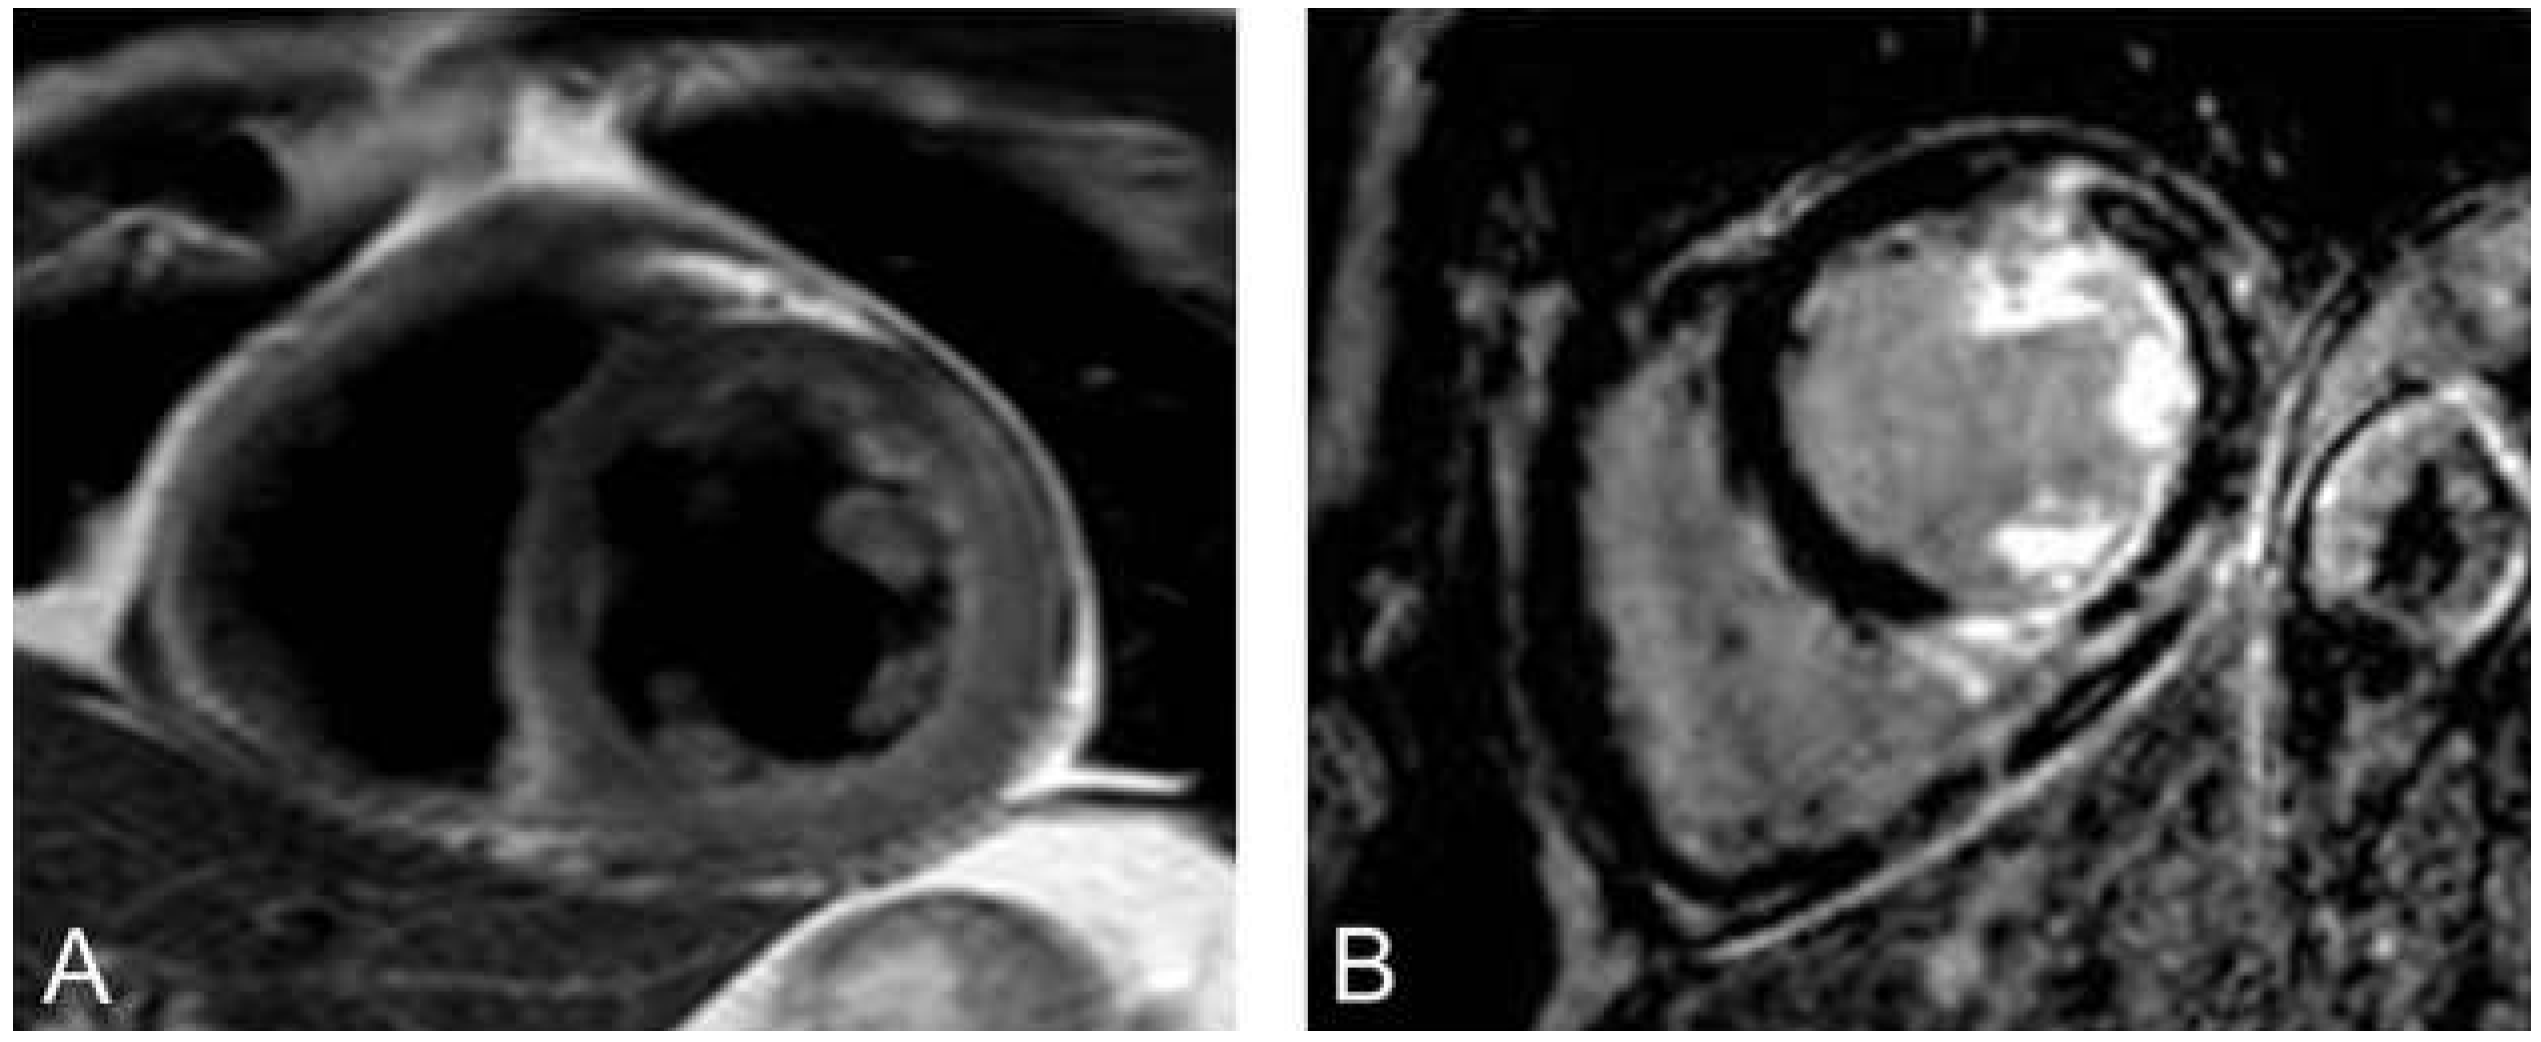

Kardiale Thromben

Eine Komplikation, die wesentlich zu Mortalität und Morbidität herzinsuffizienter Patienten beiträgt, ist das Auftreten eines Ventrikelthrombus (Figure 4). Sowohl bei Patienten mit ischämischer Kardiomyopathie als auch bei Patienten nach akutem Myokardinfarkt können linksventrikuläre Thromben auftreten. Das Herz-MRI zeigt die höchste Sensitivität und Spezifität zur Detektion von Ventrikelthromben verglichen mit der transösophagealen bzw. transthorakalen Echokardiographie und auch der kontrastmittelverstärkten Echokardiographie [58,59].

Figure 4. Figure 4. Darstellung eines Thrombus im LV-Apex. Sichtbar sowohl in den Cineaufnahmen im 4- und 2-Kammer-Blick (A,B) als auch in den Late-gadolinium-enhancement-Aufnahmen im 4- und 2-Kammer-Blick (C,D).